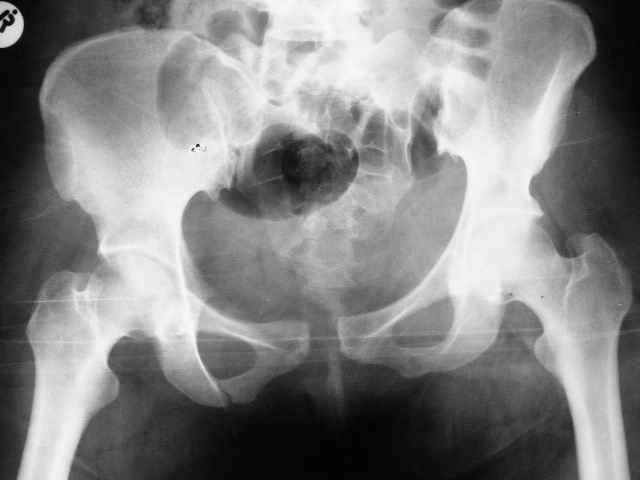

Больная 28 лет от роду попала в ДТП 12.12.04Что бы вы предложили.заранее признателен,Евгений И Чекашкин

У нас бы аппаратом все вправили, потом ввели закрыто винты через крестцово-подвздошное, а сперелди - пластину.

Сегодня утром прооперировал: на симфиз пластину на 4 винтах и два 6.5 мм винта с неполной резьбой на левое крестцово подвздошное сочленение. (пришлось открыть - девушка весьма внушительной комплекции и пропальпировать крыло и ости не представлялось возможным, спасительного в таких случаях набора канюлированных винтов в госпитале нет). Проконтролировал качество репозиции ЭОПом - остался доволен.

При таких переломах я применил бы ургентно в первый же день поступления переднюю фиксацию таза, хотя спереди, но создастся относительная стабилизация таза.

Наружный фиксатор на уровне spina anterior inferior в месте прикрепления прямой головки четырехглавой, где хорошая масса кости, провожу стержень под углом в направлении sciatic notch, который фиксируется дуговым стержнем, как на снимке, но возможны и другие различные варианты.

С первого дня создается стабильность таза, дает время на обдумывание плана, затем при желании перевод к передней фиксации пластиной, а потом только перкутанный метод фиксацию rрестцово-подвздошного сочленения.

Женя, привет! Поностью согласен с Джолдасом, только дал бы тягу за правую ногу по длине с гтперкоррекцией, а потмо наложил аппарат с 2-мя стержнями с каждой стороны в надацетабулярной зоне под острым углом друг к другу. Если же совсем упростить и сделать конфетку из ... то можно больног туго запеленать через крылья и вертелы и зашить - постельгый режим до 1,5 - 2 мес. А еще раньше мы таких лечили в гамаке. А сейчас, если ты помнишь наши разговоры о тазе - оперируем в cрочном порядке после подготовки из надлобкового доступа большими пластинами на 10 - 12 отв., которые позволяют после домоделирования восстановить конфигурацию тазового кольца и устранить смещение и спереди и сзади. Поднимать можно на следующий день без опоры на левую ногу на стороне порвежденного КПС, если хочешь м опорой - то надо еще 2 винта провести через КПС закрыто. ЛАФ.